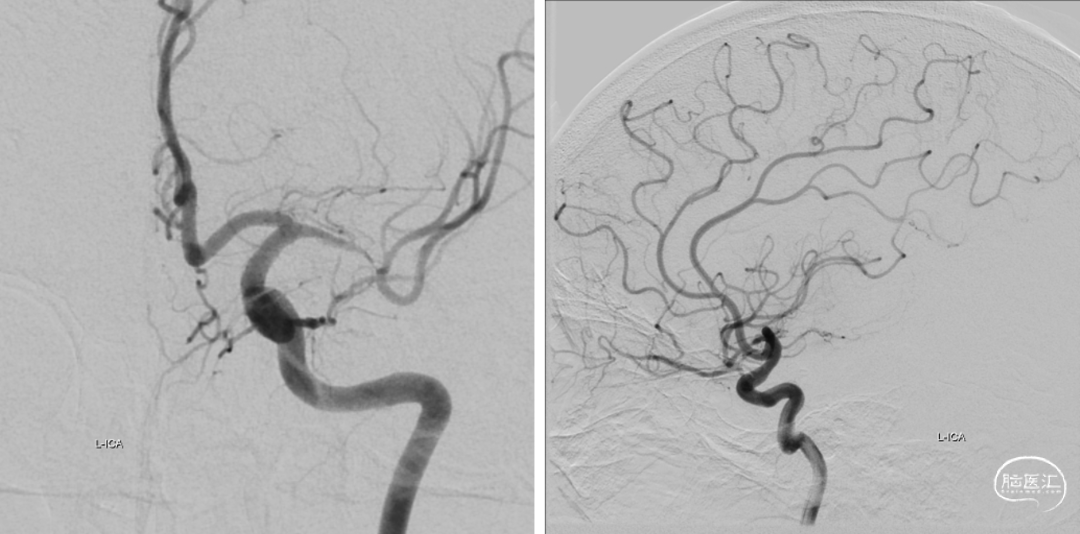

DSA

重要影像结论:左大脑中动脉M1末端重度狭窄。

病变部位:左大脑中动脉M1末端

远端正常血管直径(mm):1.99

狭窄处最小直径(mm):0.2

病变长度(mm):8.59

狭窄度(%):90%